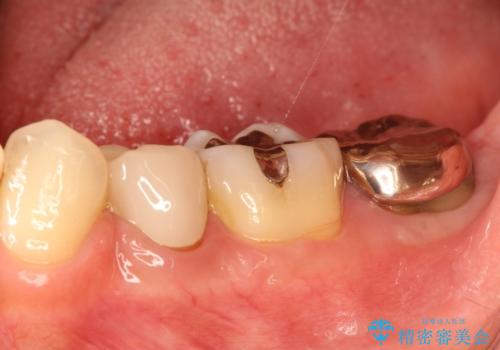

奥歯が痛い。根管治療からセラミッククラウン

- 奥歯が痛いことを主訴に来院されました。

レントゲンにて根尖病変を認め、根管治療を行ったのちセラミッククラウンにて修復しました。根管治療は川島先生に依頼。

咬合力が強くかかる部分には欠けるリスクのほとんどない金属を用いることが最良ですが審美性に劣ります。

今回は白い材料での修復を希望されたため、セラミッククラウンにて治療を行いました。